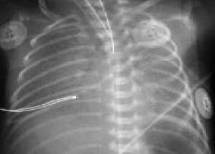

Выраженное снижение пневматизации легких, воздушные бронхограммы, границы сердца практически не различимы, стёрты (Рис.6).

Рисунок 6. РДС. Рентгенограмма грудной клетки в прямой проекции, в горизонтальном положении. Интенсивное мелкоточечное затемнение легочных полей - с-м "матового стекла", на фоне которого не дифференцируется тень средостения. Визуализируются линейные просветления, обусловленные заполненными воздухом бронхами - "воздушная бронхограмма". (Диагностика и лечение РДС недоношенных // метод. рекомендация, 2007)